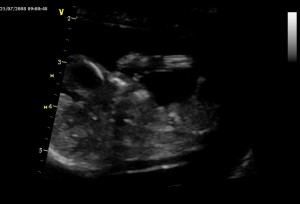

První dvě fotky jsou z 25.7., to byla maminka na začátku 14 týdne těhotenství. Tady jsem vidět ještě krásně, skoro celý, v levo hlavička a pak bříško a malá ručička. Na druhé fotce je jen detail mé hlavičky z profilu, jak si cucám paleček.